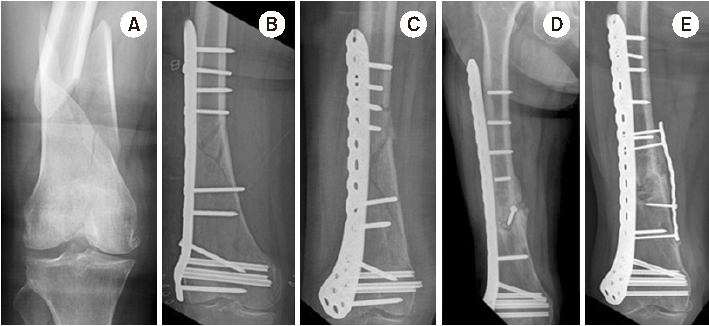

Fig. 4

(A) Distal femur fracture in a 70-year-old male. (B) Postoperative anteroposterior radiograph after minimally invasive locked plating. (C) Fixation failure along with broken locking screws two months after surgery. (D) Anteroposterior radiograph seven months after double plating showing bony union.